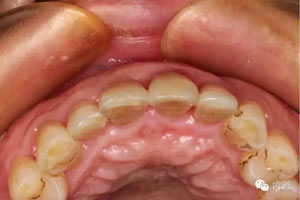

初診照片(合面照)